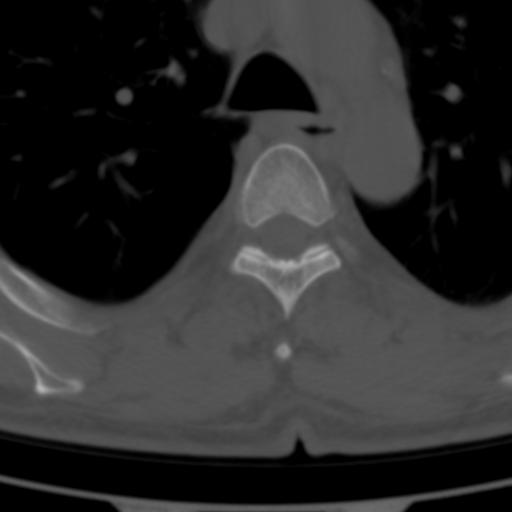

标题: CT25189:胸椎ct,请会诊!

既往食管癌,现行ct检查!

中上段食道癌,椎体轻度退变。

支持中上段食道癌,椎体轻度退变,必要时做ect。